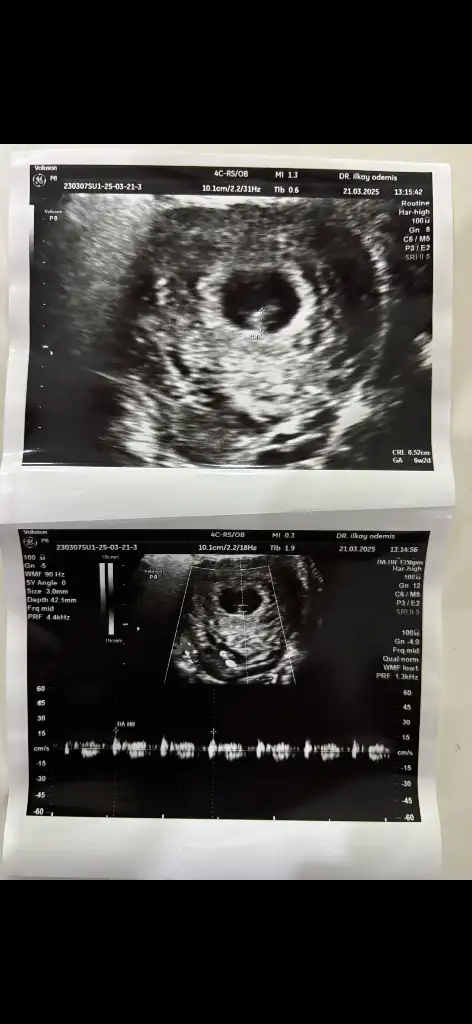

Yaa bizede bakabilir misiniz çok merak ediyorum görsellerde ilk görsel 10+4 diğer görseller 6+4 haftalık :)Pek iyi anlamıyorum ama nub teorisi fotolarına baktığım kadarıyla kız gibi görünüyor

Banada bakabilir miisniz görsel olarak yorumlara ekledim :)Merhaba ilk önce rabbim hayırlısını ve gönlünüze göre olanı versin inşallah nub teoremine göre sanki kız gibi

Banada bakabilir miisniz görsel olarak yorumlara ekledim :) ilk görsel 10+4 diğer görseller 6+4 haftalıkken karından ultrasonla bakıldı

Sizce benimki ne olabilir ben erkeğe benzetiyorum ama eminde değilim kız diyenlerde olduMerhaba nub teoremine gore kiza benzettim ben ama rabbim go lunuze gore versin insallah